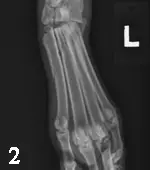

Left tarsal radiographs: Lateral and dorsoplantar (DP) views

Radiographic Findings (Figures 1 and 2):  There is an oblique fracture of the proximal diaphysis of the 2nd metatarsal bone with minimal displacement. There is displacement of all metatarsal bones dorsally relative to the distal row of tarsal bones. This is best visualized in the lateral view. In addition, there is also increased joint space in the tarso-metatarsal joint, which is more severe medially. The first metatarsal bone is a small rounded opacity superimposed over the abnormally widened joint space in the DP view; this should not be confused with a fracture fragment.

Diagnosis (Figure 3): These findings indicate a fracture of the 2nd metatarsal bone (arrow) and, more importantly, subluxation of the tarso-metatarsal articulation (arrowhead). In human medicine, this is called a Lisfranc injury and is most commonly identified in athletes.